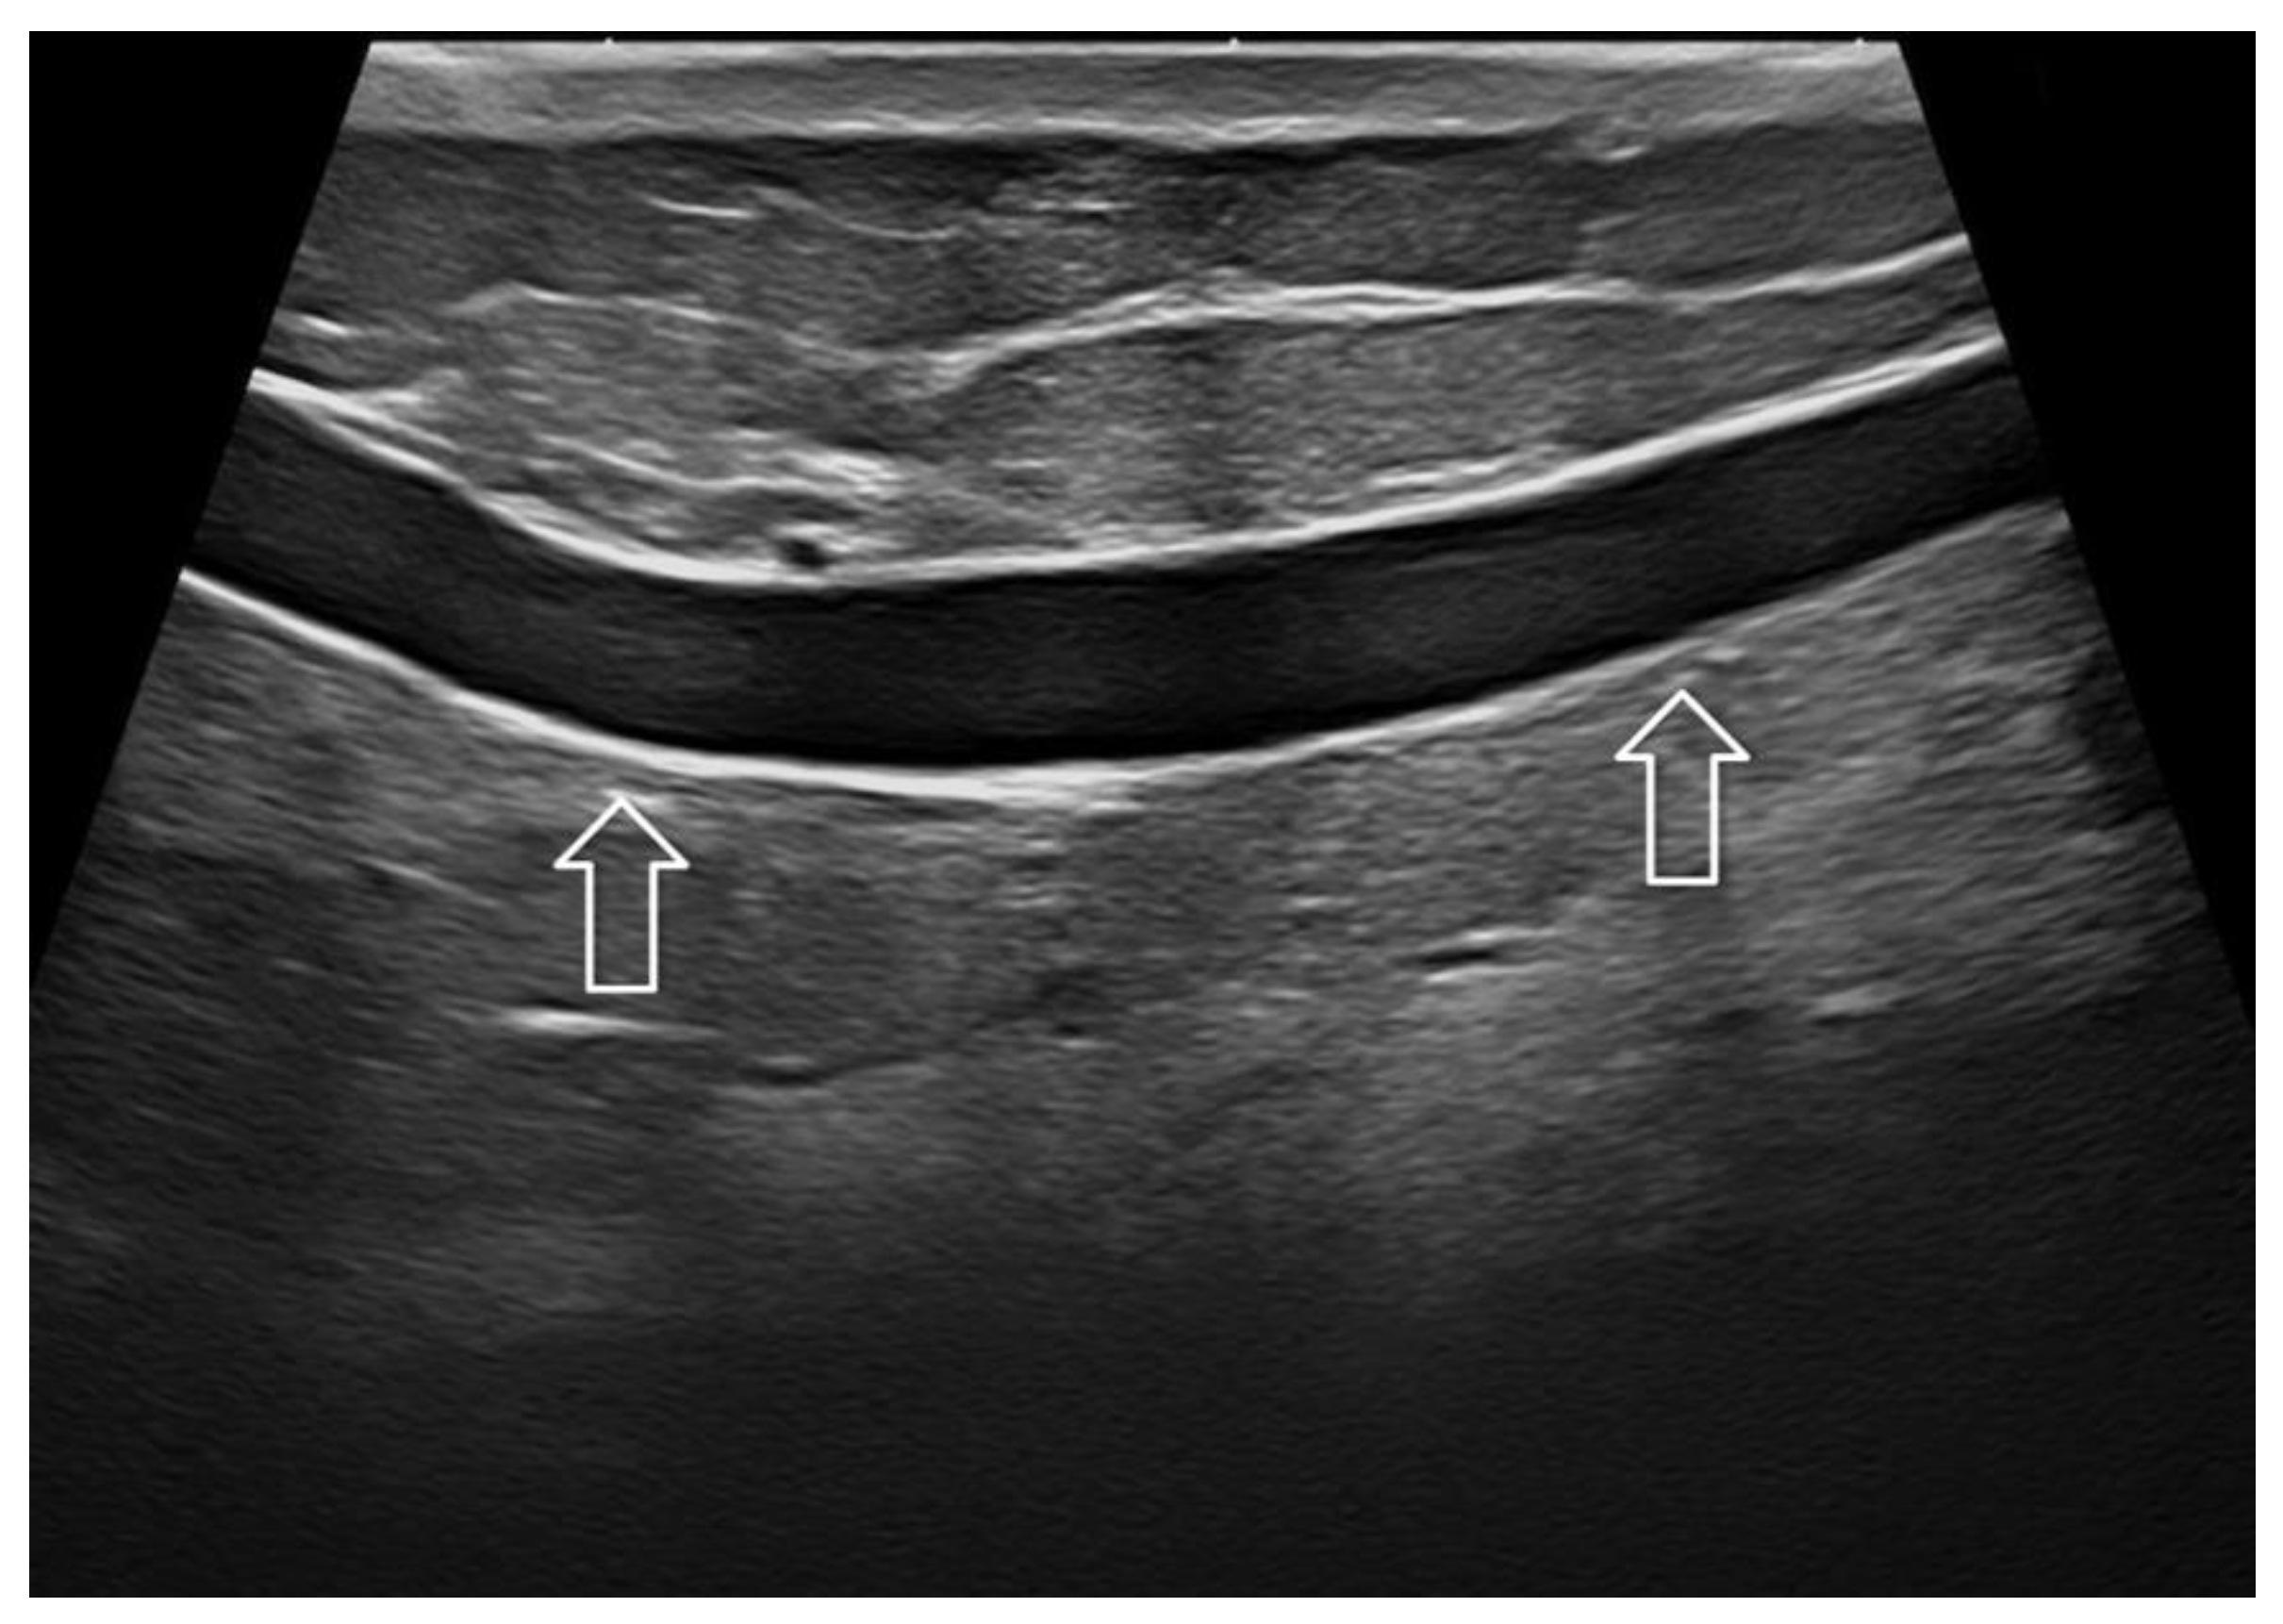

Figure 3. Skin thickening after conservative breast surgery and adjuvant irradiation. Imaging at 22 MHz allowed an optimal depiction of the thickened dermis (white arrow) and hypodermis (gray arrow).